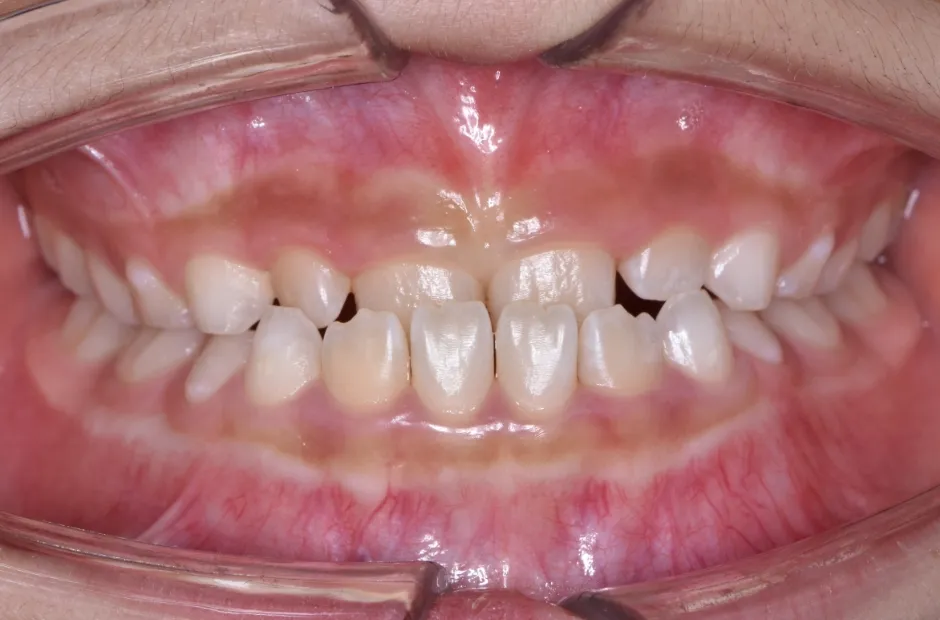

叢生

| 診断名・主訴 | 叢生 |

|---|---|

| 年齢・性別 | 10歳・女性 |

| 治療期間・回数 | 2年半 |

| 治療に用いた主な装置 | 拡大床装置 |

| 抜歯部位 | なし |

| 治療費 | 30万円(税抜) |

| リスク・副作用 | 装置による違和感・疼痛・歯肉退縮・歯根吸収・虫歯のリスクなど |

治療前

治療中

治療後